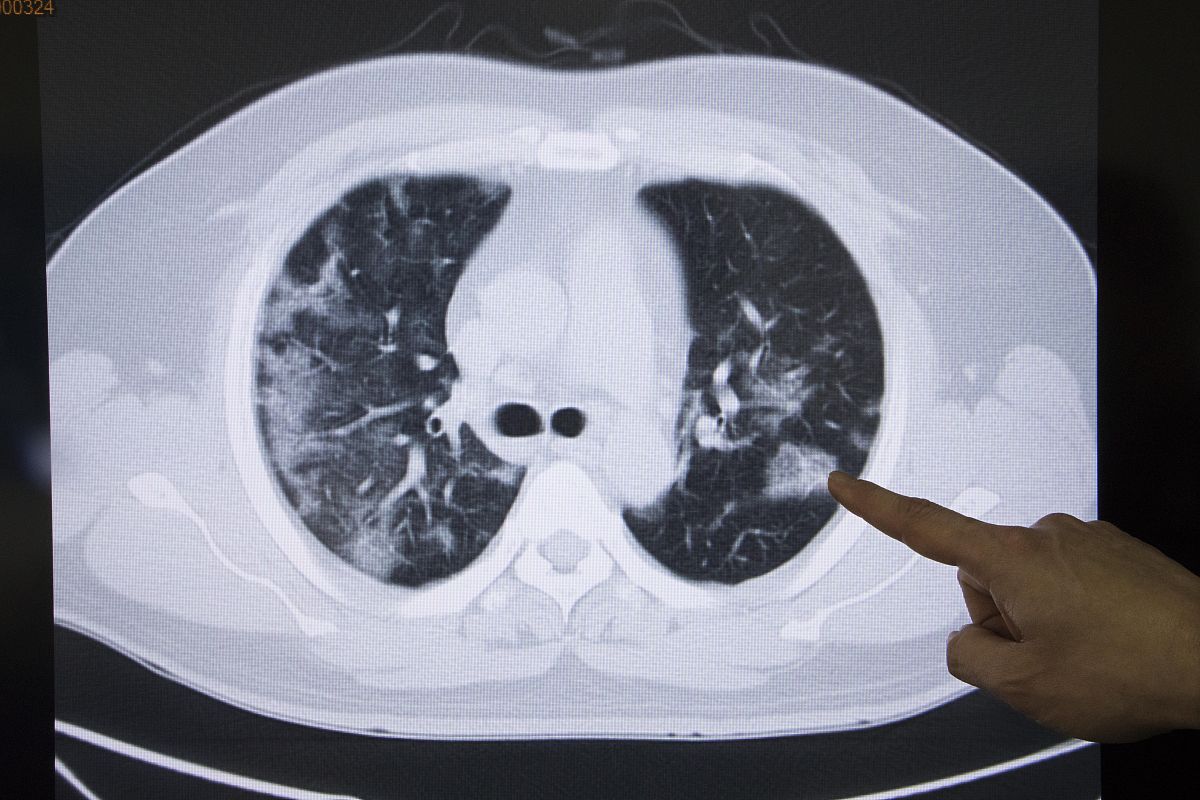

肺癌早期的影像学表现可以有以下几种:

1. 小结节:肺癌早期常呈现为直径小于3厘米的结节状病变,常见于肺实质内。这些小结节可以是实性的(有实质成分)或是磨玻璃样的(无实质成分),且通常在CT扫描中呈现为圆形或卵圆形。

4. 磨玻璃样结节:肺癌早期还可以呈现为磨玻璃样结节,这种结节在CT扫描中呈现为部分透明或半透明的病变,常常与周围肺实质之间有模糊的界限。

需要注意的是,早期肺癌的影像学表现多样,不同类型的肺癌可能呈现出不同的特点。因此,如果怀疑患者可能患有肺癌,应及时进行CT扫描等影像学检查,以确定诊断。

肺癌早期影像学表现:CT扫描识别关键征象